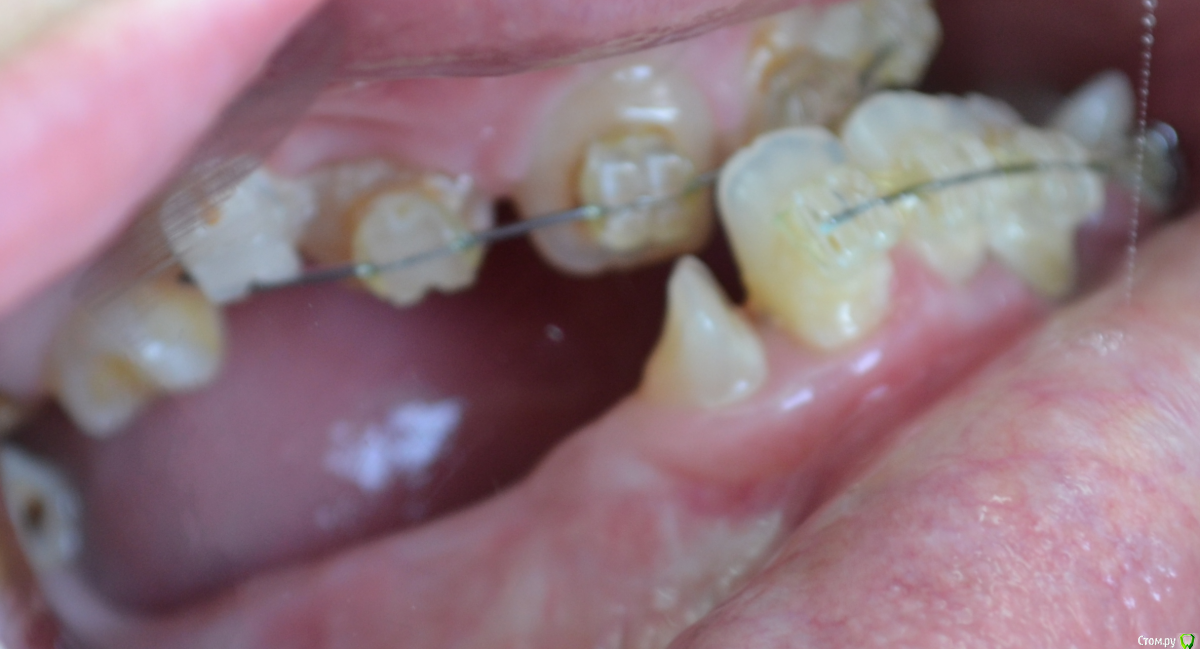

nikor117 Опубликовано 14 октября, 2015 Поделиться Опубликовано 14 октября, 2015 Здравствуйте, уважаемые коллеги.Извиняюсь за качество фото. Хотелось бы помочь пациентке 28 лет. В общем ситуация видна по фото. Сам я ортопед опыта в таких ситуациях нет, возможно подскажете куда ей стоит обратиться. Заранее спасибо. Если нужна дополнительная информация скажите постараюсь выложить. Ссылка на комментарий

nikor117 Опубликовано 14 октября, 2015 Автор Поделиться Опубликовано 14 октября, 2015 Возможность красиво улыбаться, с ее слов на ортодонтии она уже порядка 8 лет, брекеты стоят 1.5 или 2 года, сама врач, сложность ситуации представляет, хочет услышать совет Ссылка на комментарий

Yana guapa Опубликовано 14 октября, 2015 Поделиться Опубликовано 14 октября, 2015 эти фото были ведь на соседнем форуме "...." . там были советы, и хирурги и ортодонты отписывались. причем не так давно. и фото были без брекетов, до начала лечения (около 6 месяцев назад). не похоже на 1.5 года с брекетами здесь . тем, что у нее на зубах стоит сейчас - не помочь это точно. 4 Ссылка на комментарий

Monkey Опубликовано 18 октября, 2015 Поделиться Опубликовано 18 октября, 2015 (изменено) и мне, пожалуйста у пациентки похоже синдром Крузона Изменено 18 октября, 2015 пользователем Monkey 1 Ссылка на комментарий